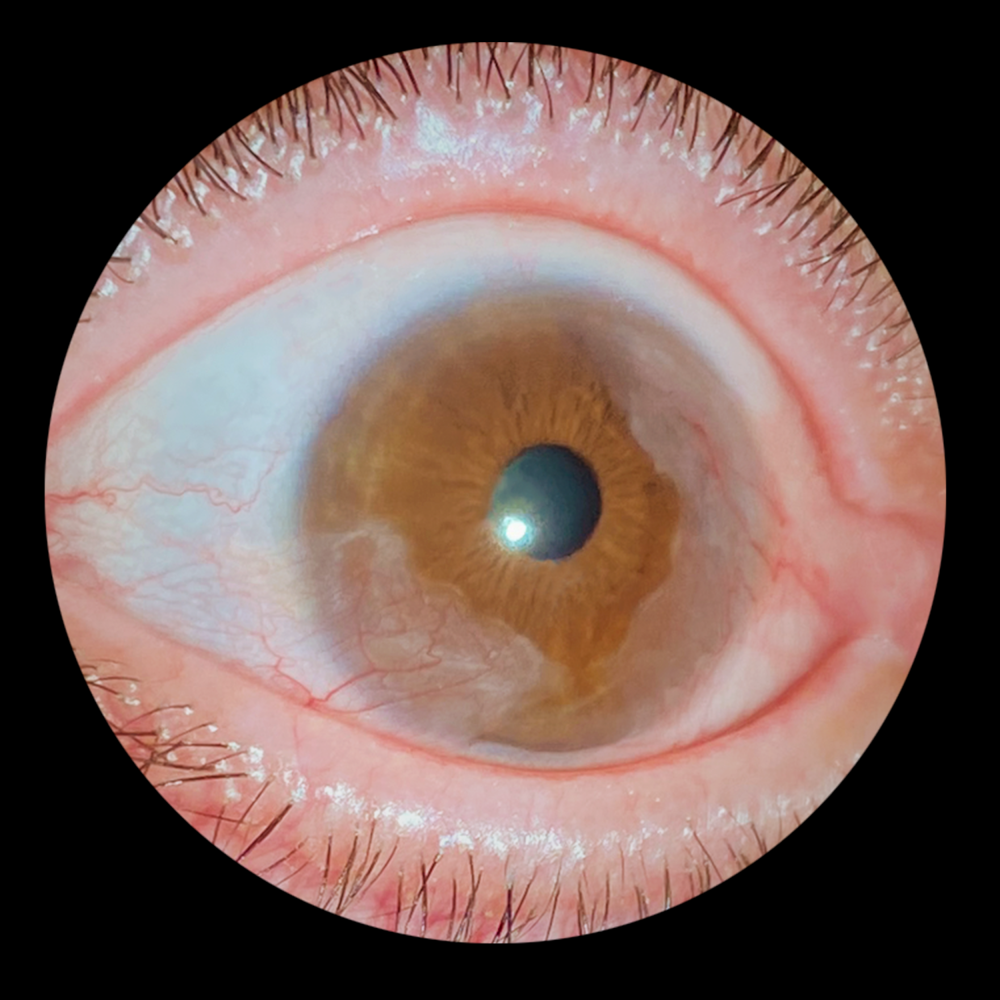

Título: Bilateral Aniridia with Microspherophakia, Posterior Polar Cataract, and Lens Subluxation

Autor: João Castro Cabanas

Coautores: Pedro Moreira Martins, Filipe Sousa-Neves, Sidnei Barge

Instituição: Unidade Local de Saúde Gaia e Espinho

Descrição: Intraoperative photograpgh of a 3-month-old boy The image shows microspherophakia with posterior polar cataract, which appears less dense in the left eye, and subluxation of the lens towards the nasal region. Iris hypoplasia is evident, along with centripetal lenticular vascularization extending onto the anterior lens capsule.